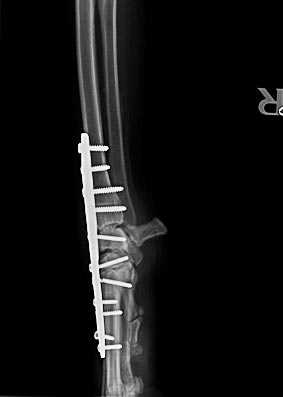

Kurz vor Weihnachten 2016 hat Carla sich beim Toben einen Bruch und kompletten Bänderriss im Karpalgelenk zugezogen.

Nachdem das Gelenk mit einer Platte und 11 Schrauben versteift wurde, mussten wir sie monatelang schonen.